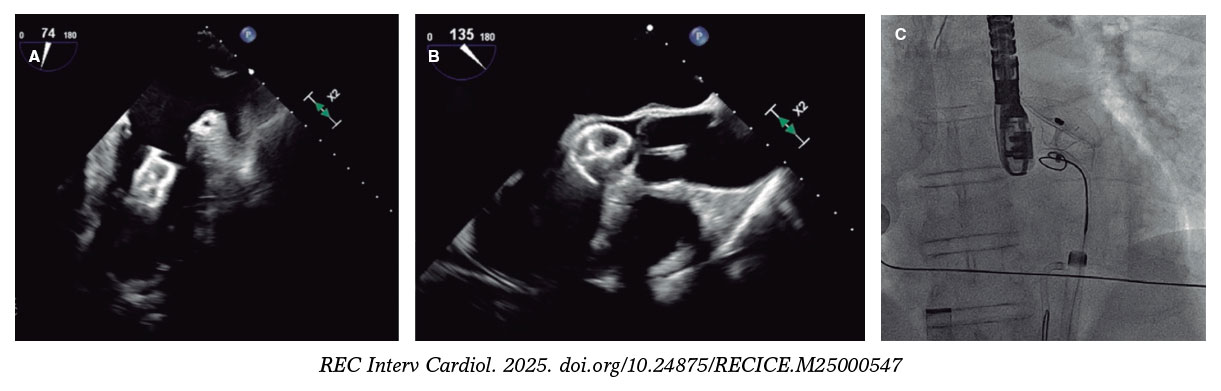

Figure 5 and figure 6 illustrate examples of left atrial appendage device embolization.

Figure 5. Intraoperative transesophageal echocardiography (TEE) and fluoroscopy of left atrial appendage closure with a 25-mm Amulet device. A: the device migrated to the left ventricle (LV). B: an 8-Fr JR4 guiding catheter with a 20-mm snare was introduced via left femoral access, capturing the device by the distal lobe screw and allowing it to be pulled into the descending aorta. C: afterwards, the right femoral artery was cannulated with a 16-Fr introducer sheath; using a guiding catheter and a 30-mm snare, the device was again captured by the distal lobe screw, pulled back, and finally extracted.